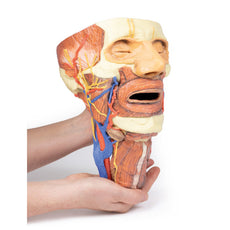

3D Printed Sagittal Section of Head with Infratemporal Fossa Dissection

3D Printed Sagittal Section of Head with Infratemporal Fossa Dissection

This 3D model provides a combined midsagittal section through the head and

superior neck coupled with a deep dissection into the infratemporal fossa

region and superficial dissection of the scalp.

On the opposing side of the model, a superficial and deep dissection has

opened a large window into the anatomy of the lateral scalp and infratemporal

fossa. Across the scalp there is a well preserved posterior auricular nerve

and superficial temporal artery highlighted on the superficial surface of the

temporalis muscle. Anteriorly, the temporalis has been dissected to expose

the deep temporal arteries arising from across the maxillary artery.